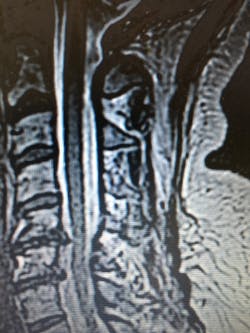

I encouraged my primary care doctor to order another MRI, which would be the third in five years. The results were shocking because the herniations of C5-7 were very large and the disc desiccations and osteophytes were right there in black and white.

A friend who was an anesthesiologist referred me to the Tucson Orthopedic Institute. We made an appointment with Dr. Jeffrey Baron, an orthopedic surgeon. Dr. Baron was a no-nonsense individual and blatantly stated that cervical spine surgeries statistically do not have favorable outcomes. He was not optimistic that I would be rid of my headaches or neck pain. He did not want to hear what any other physician had said about my condition and did an initial exam and x-rays.

After viewing the films, he agreed that an anterior discectomy/laminectomy and fusion of Cervical 5-7 with a bone graft was the best surgical procedure. He outlined in detail what the procedure included from beginning to end, and he expressed his confidence in actually performing the procedure. He left the decision up to me, and I quickly made the choice to schedule the surgery and try what may be my last resort.